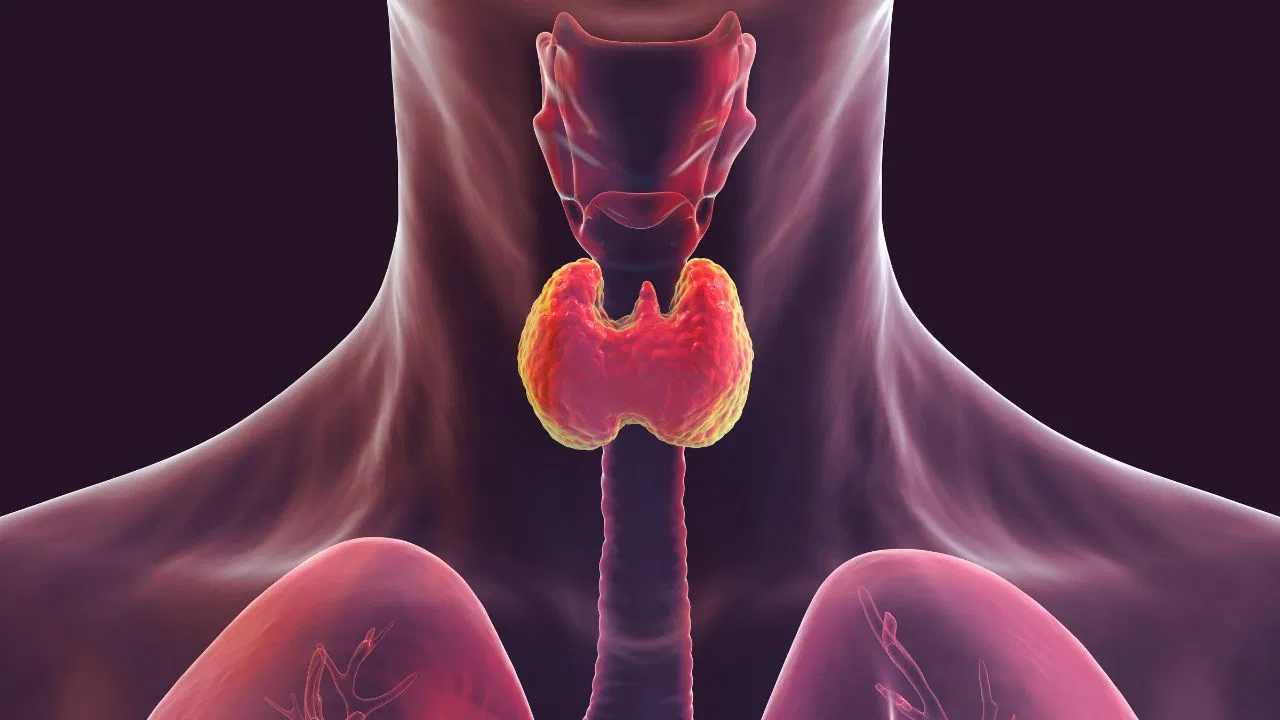

Thyroid Control Tips : आज की भागदौड़ भरी जिंदगी और असंतुलित खान-पान के कारण थायरॉइड एक गंभीर स्वास्थ्य चुनौती बनकर उभरा है। थायरॉइड दरअसल हमारी गर्दन के निचले हिस्से में स्थित एक छोटी सी ग्रंथि होती है, जो तितली के आकार की दिखती है। यह ग्रंथि शरीर के मेटाबॉलिज्म (उपापचय) को नियंत्रित करने वाले महत्वपूर्ण हॉर्मोन बनाती है। जब यह ग्रंथि जरूरत से ज्यादा या कम हॉर्मोन बनाने लगती है, तो शरीर का संतुलन बिगड़ जाता है। इसके परिणामस्वरूप अचानक वजन बढ़ना या घटना, अत्यधिक थकान, बालों का झड़ना और चिड़चिड़ापन जैसे लक्षण दिखाई देने लगते हैं।

Thyroid Control Tips : महिलाओं में बढ़ता जोखिम और थायरॉइड के मुख्य कारण

आंकड़ों के अनुसार, पुरुषों की तुलना में महिलाओं में थायरॉइड की समस्या अधिक देखी जाती है। विशेष रूप से गर्भावस्था, मेनोपॉज या उम्र बढ़ने के साथ हार्मोनल बदलावों के कारण यह ग्रंथि प्रभावित होती है। इसके पीछे मुख्य कारणों में अत्यधिक तनाव, नींद की कमी, खराब जीवनशैली और पोषण युक्त भोजन का अभाव शामिल है। थायरॉइड को साइलेंट किलर भी कहा जाता है क्योंकि इसके लक्षण शुरुआत में बहुत सामान्य लगते हैं, लेकिन लंबे समय में यह शरीर के अन्य अंगों को भी प्रभावित कर सकता है।